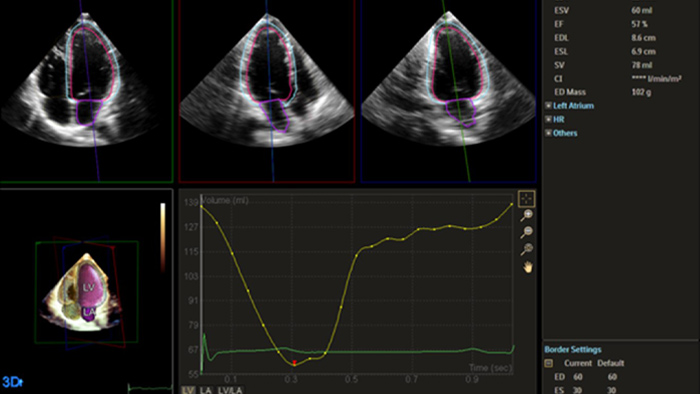

Quantification through Dynamic HeartModel.

Robust and reproducible imaging tools are important to diagnose and monitor disease progression in heart failure. Current guidelines support the use of advanced echocardiography tools such as longitudinal strain and 3D assessment of LV and RV volumes and function.

Automation for robust, proven reproducible cardiac quantification in both 2D and 3D.